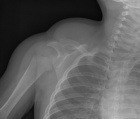

Patient is a 15 month old female who presented after her babysitter noticed a lump on her R. shoulder; PMH: Otitis Media

Physical Exam: Large erythematous mass over R. shoulder and supraclavicular region; normal R. UE sensation/motor

Zoom image: Radiological image Radiological image.